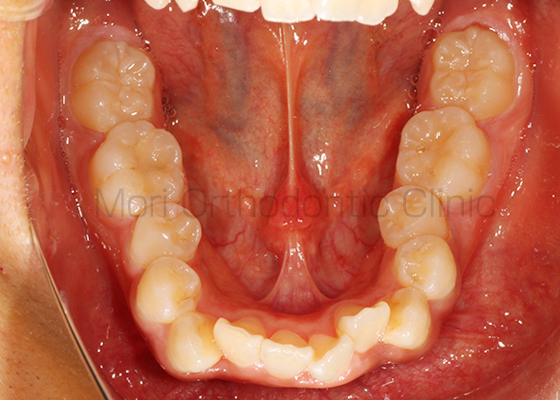

術前

術後

| 主訴 | 歯並び、八重歯 |

|---|---|

| 診断名 | AngleⅡ級叢生 |

| 年齢 | 30歳2か月 |

| 治療装置 | Multi-Bracket(表側矯正)、CARRIERE DISTALIZER |

| 抜歯部位 | 14,24,35,45 |

| 治療期間 | 2年1か月 |

| 治療費 | 825,120円(税込) |

| リスク・副作用 | 矯正治療による歯の移動に伴う痛み、歯根吸収、歯肉退縮、虫歯 |